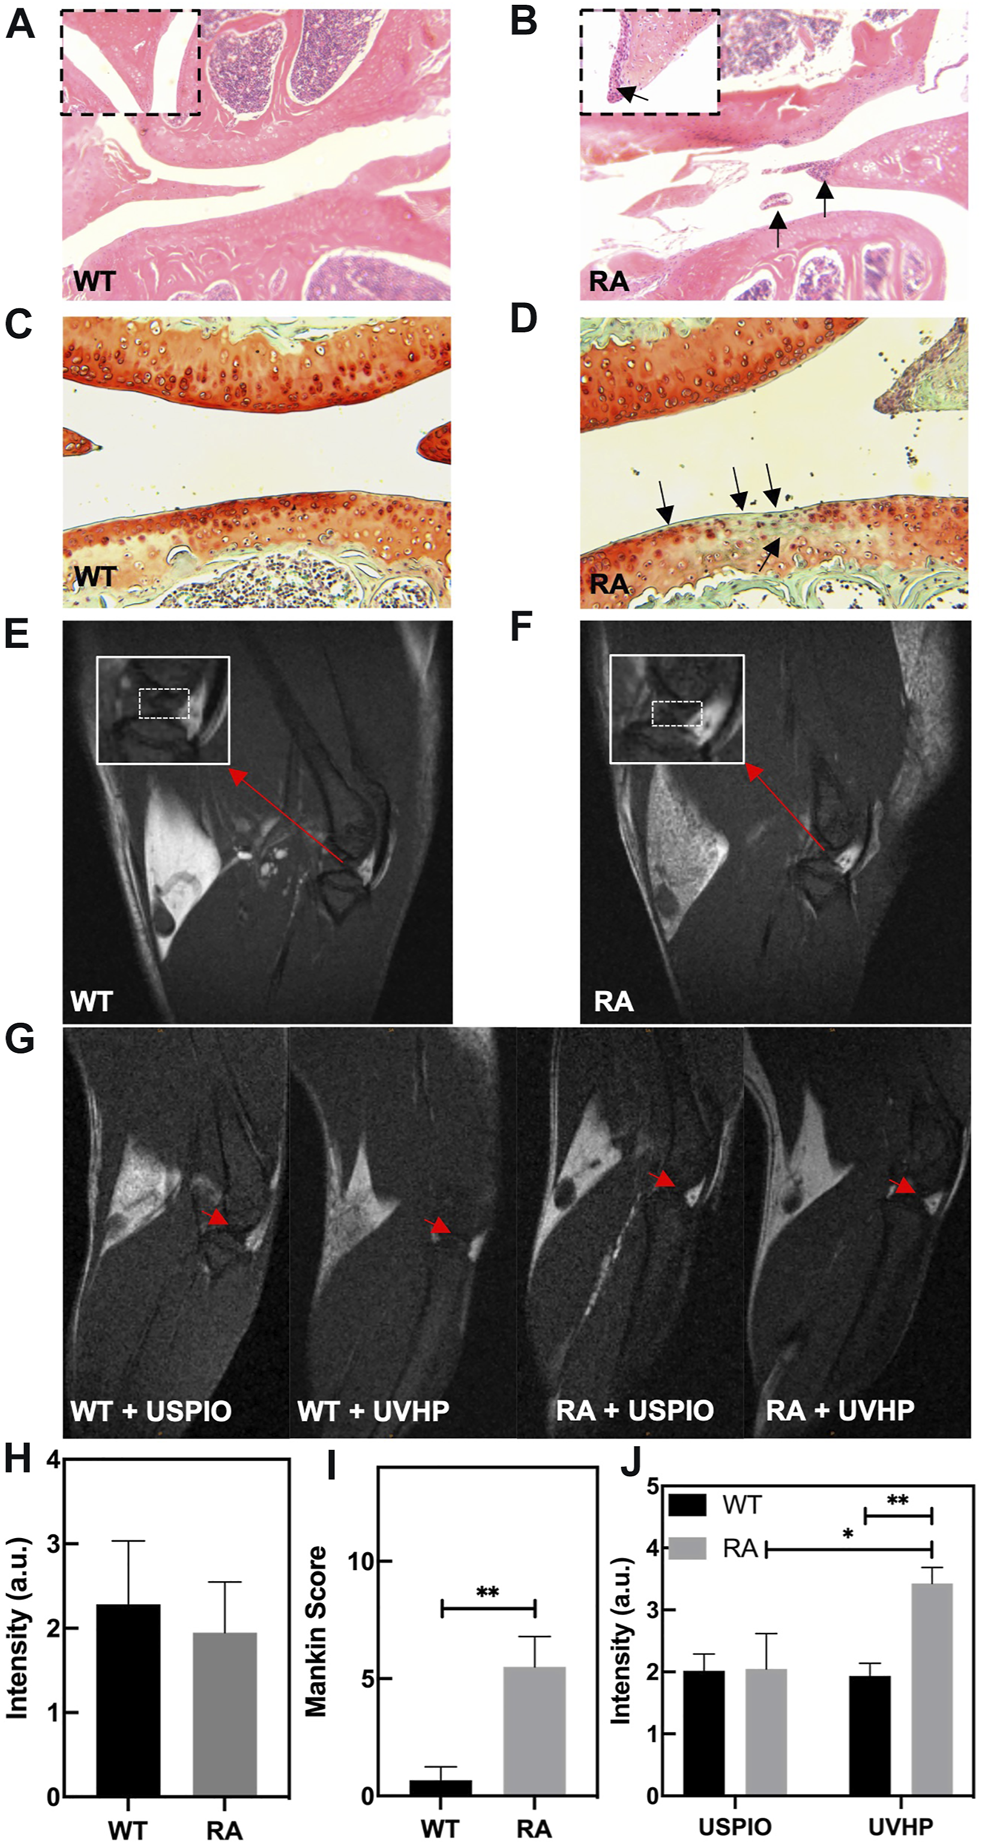

Compared with normal mice (Figure 5A), there are inflammatory cells immersed in the knee joint and the synovium observed in the RA model mice (Figure 5B). The safranin O/fast green staining showed that the cartilage structure of the RA model mice (Figure 5D) was destroyed. The cartilage surface was rough, and the cartilage cells were decolorized. The Mankin score (Figure 5I) of the RA model mice was significantly higher than that of WT mice, and it was in the early stage (Ehrlich et al., 1978). These results indicate that we established the RA model mice successfully.

FIGURE 5. Photomicrographs of representative hematoxylin and eosin (H&E)–stained sections of knee joint from WT mice (A) and RA mice (B). The arrow shows the infiltration of inflammatory cells. (C,D) Safranin O/fast green staining sections of knee joint from WT mice (C) and RA mice (D). The arrow shows the cartilage layer lesion area. (E,F) T1-weighted MRI of the knee joint in WT and RA mice; red arrows indicate the site of interest. (G) T1-weighted MRI of the knee joint in WT and RA mice injected with UVHP through the tail vein, at the same time WT and RA mice injected with USPIO in the tail vein as controls; red arrows indicate the site of interest. (H) MRI signal value of T1-weighted MRI of the knee joint in WT and RA mice. (I) Mankin score of knee joints in WT and RA mice. (J) Signal value of T1-weighted MRI of the knee joint in WT and RA mice injected with USPIO and UVHP, respectively.

To confirm the targeting joint MRI effect of UVHP on RA mice, first, we performed T1-weighted MRI on normal WT and RA mice, respectively. As shown in Figures 5E, F, the area framed by the dashed line is the synovial fluid region between the joints. Our statistics for this part of the area showed that there was no significant difference between normal WT and RA mice (Figure 5H).

Next, we injected USPIO and UVHP to normal WT mice and RA mice via the tail vein, respectively; 24 h later, we performed a T1-weighted MRI of the joint area (Figure 5G). The signal values of the synovial region between the joints were counted, and the results are shown in Figure 5J. There was no significant difference in signal values between WT and RA mice after USPIO injection, but the signal values of RA mice were significantly higher than those of WT mice after UVHP injection (Figure 5J). This indicates that more UVHPs were enriched at the joint region of RA mice, whereas USPIO was not enriched at that region. These results proved that UVHP could be targeted to joints of RA mice. To further confirm that UVHP could target the RA region, the changes of Fe content in the knee joint were tested by ICP-OES. The results show that there was no significant difference in Fe content in the knee joints of the WT and RA mice injected with USPIO, but the RA mice injected with UVHP showed a significant increase in Fe content in the knee joints of RA mice (Figure 6A), which was consistent with our MRI results (Figure 5J). This indicates that UVHP could target the joints of the RA model mice.